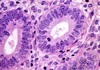

Aspecto histológico glândula serosa?

Histologia: Tecido Epitelial Glandular

Glândulas exócrinas

Serosas?

Secretam um fluido aquoso rico em enzimas.

(pâncreas)